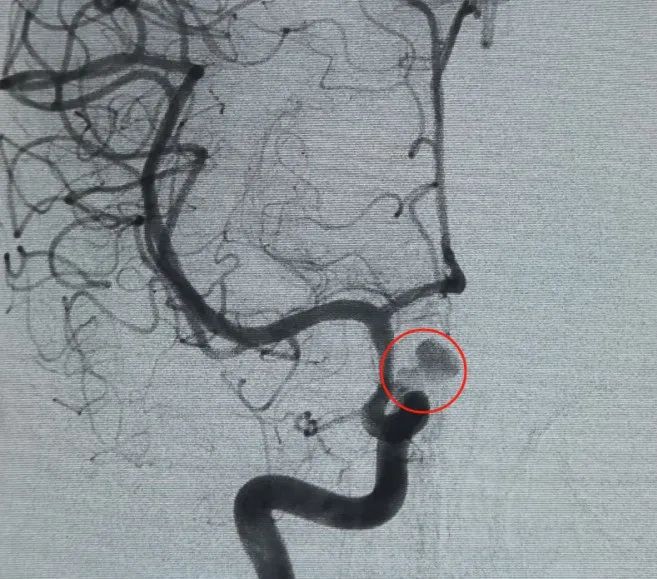

Diagnóstico: artéria carótida interna esquerda segmento C6 artéria oftálmica aneurisma

Um Perfiller®3mm × 6 cm bobina expansível e um Perfiller®3mm × 2 cm bobina expansível foram então colocados para completar a oclusão do pescoço. Posteriormente, uma Nuva®Desviador de fluxo (TJED-D-5.0-16) foi entregue e implantado no pescoço do aneurisma. A angiografia de seguimento tanto na visão anteroposterior quanto na lateral confirmou excelente cobertura, boa aposição da parede e clara radiopacidade, com acentuada estagnação do contraste.